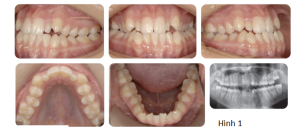

Phân tích case: Chỉnh nha tiền phẫu thuật cho bệnh nhân bị móm, hàm dưới đưa ra trước và lệch trái

Bệnh nhân có kiểu xương hạng III với thiểu sản xương hàm trên và xương hàm dưới đưa ra trước, lệch nhẹ sang bên trái. Bệnh nhân có tăng kích thước dọc, với độ lộ răng cửa tối thiểu ở tư thế nghỉ và lộ hoàn toàn khi cười. Đưa xương hàm trên ra trước sẽ giải quyết được tình trạng lõm mặt khi nhìn nghiêng và kết quả là tăng độ lộ răng cửa nhiều hơn, cho thấy có thể cần tác động vào phần trước xương hàm trên. Lực tác động vào phần sau xương hàm trên (lớn hơn lực tác động vào phần trước, nghĩa là đẩy không đồng nhất) được yêu cầu để giải quyết độ cắn trùm giảm và xu hướng cắn hở phía trước (móm). Lùi xương hàm dưới kết hợp xoay sang bên phải sẽ giải quyết được tình trạng xương hàm dưới đang nhô ra và bất cân xứng.

Qua thăm khám, bác sĩ chỉ định bệnh nhân cần chỉnh nha trước phẫu thuật hàm. Và các mục tiêu điều trị chỉnh nha bao gồm:

- Làm đều và làm phẳng các cung răng: Dàn đều răng bằng cách sử dụng dây cung đàn hồi ở thời điểm bắt đầu chỉnh nha tiền phẫu thuật. Làm phẳng cung răng thực hiện chủ yếu bằng dây cung SS (thép không gỉ).

- Phối hợp 2 cung răng: Đánh giá sự phối hợp 2 cung răng trong tương lai được thực hiện thông qua mẫu hàm nghiên cứu trước điều trị. Trong trường hợp này, phần nong rộng cần thiết ở cung răng trên có thể đạt được nhờ sử dụng dây cung bằng thép không gỉ hình chữ nhật.

- Làm mất bù trừ: Trong trường hợp này, cần làm mất bù trừ của cung hàm trên và hàm dưới để tạo ra độ cắn chìa âm phù hợp trước phẫu thuật và cho phép các dịch chuyển phẫu thuật mong muốn để hoàn toàn thúc đẩy sự thay đổi mong muốn trên gương mặt.

Việc làm mất bù trừ của cung hàm trên đòi hỏi phải dựng trục nhóm răng trước hàm trên. Điều này đạt được bằng cách nhổ các răng cửa bên hàm trên có kích thước nhỏ để tạo ra khoảng trống thích hợp. Ở cung hàm dưới, việc làm mất bù trừ đạt được bằng cách làm nghiêng ngoài các răng cửa hàm dưới.

- Duy trì đường giữa hàm dưới với đường giữa cằm: Trong trường hợp này, cung hàm dưới được điều trị không nhổ răng. Vì đường giữa hàm dưới trùng với cằm ở thời điểm bắt đầu chỉnh nha tiền phẫu thuật, nó được duy trì trong suốt giai đoạn làm phẳng và làm đều cung hàm dưới.